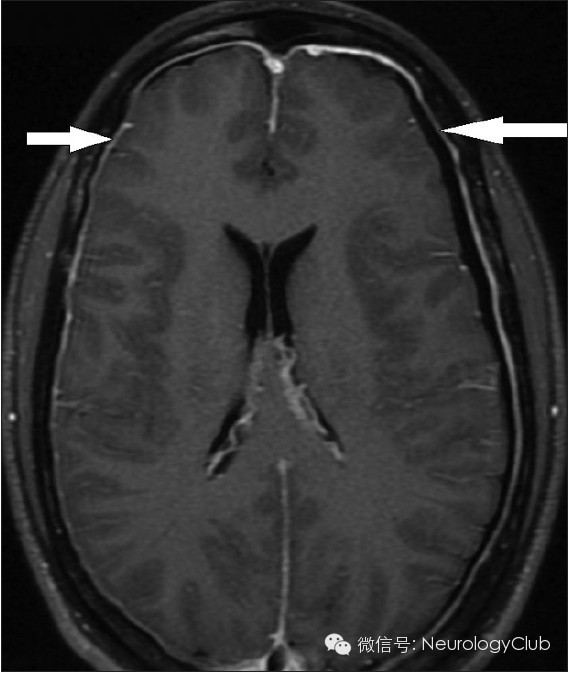

硬膜下积液表现为双侧对称性薄层积液,无占位效应,对下面的脑沟脑裂无压迫效应。

增强扫描时硬脑膜弥漫性增强增厚是颅内低压综合征的最具特征性表现,也是阳性率最高、出现最早的MRI表现。呈不间断的线样增强,无局限性结节,同时经常伴有硬脑膜增厚和皮层静脉的扩张,但从不累及软脑膜。

(3)静脉结构充盈(Engorgement of venous structures)

(静脉窦扩张变圆)